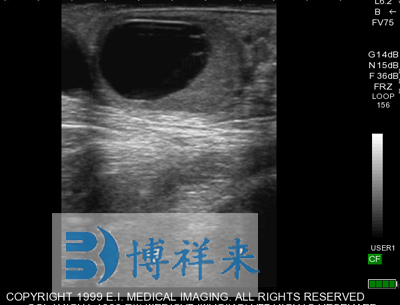

| 适应条件 | 防水、防尘、防摔击 | 显示模式 | B模式,B+M模式(B模式下M线可以调节) |

| 超声类型 | 数字超声 | 产科软件 | 各种动物妊娠期参数表格 |